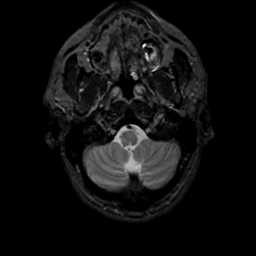

MR Study #4, March 3, 1991 -- Slice #5

[Home][Help][Clinical][Tour 1][Tour 2] Slice 5